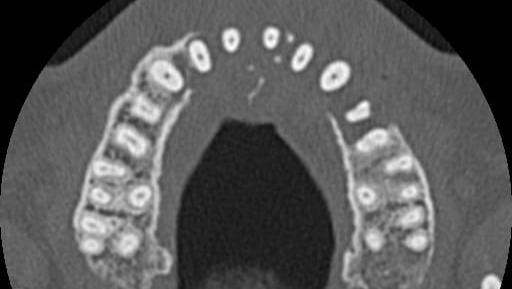

Like most cancer diagnosis, it came as a huge shock. It started with a toothache in August 2025 while we were on holiday. Edd booked himself in to see a dentist, who took standard protocol xrays, and noticed that bone was missing from the top left side of his jaw.

The dentist referred him for an urgent CT scan. The scan revealed a large mass inside the front left of his face, and surrounding bone had disappeared. The doctor wanted Edd to have an immediate biopsy, but unfortunately, we were due to fly home the following day.

Back in the UK, Edd contacted his GP, and was referred him to hospital under the "two week wait" cancer pathway. The consultant carried out another CT scan and initially believed it was a large 4cm x 4cm cyst. He thought it could be removed but would require a biopsy first for confirmation.